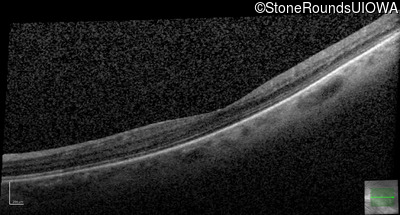

AD Familial Exudative Vitreoretinopathy (IIIE2b)

Age at visit: 32 years

This 32 year old woman has had subnormal acuity (right eye worse than left eye) since very early childhood.

AD Familial Exudative Vitreoretinopathy TSPAN12 Arg50Trp AG(G)>TG(G)   AD